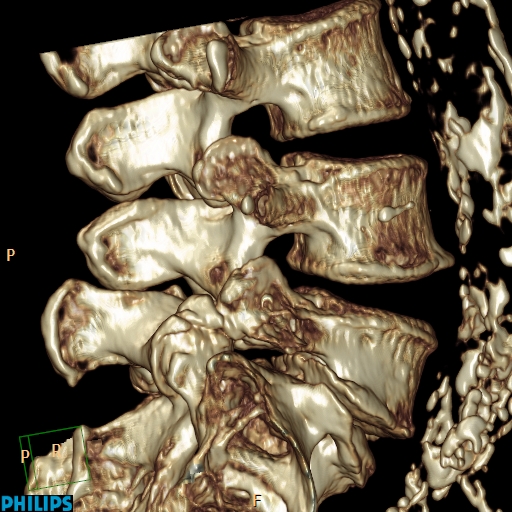

Spondylolyse et spondylolisthésis isthmique sont des aspects différents d’une affection dont la variabilité clinique est remarquable. Quantification du glissement. Clinique. Spondylolyse isthmique. Clinique. Imagerie. Formes cliniques. Indications thérapeutiques. Techniques chirurgicales.. La lyse se située plus souvent à l’étage L5/S1 mais peut parfois se retrouver à l’étage L4/L5. il est habituel que classer le glissement, occasionné par la lyse, en 4 stades de Meyerding. TRAITEMENT. Avant tout il est médical avec des antalgiques, de la rééducation associée au besoin à des infiltrations.

Spondylolisthesis de L5 sur S1 de grade III (Glissement anterieur tres important du corps

Le spondylolisthésis implique habituellement les vertèbres L3-L4, L4-L5 ou le plus souvent L5-S1. Les types II (isthmique) et III (dégénératif) sont les plus fréquents.. Dans la majorité des cas, le spondylolisthésis concerne les vertèbres les plus basses, surtout au niveau de la jonction entre la colonne lombaire et le début de la colonne sacrée. La localisation entre la 4e et la 5e vertèbre lombaire est la plus commune : on parle de spondylolisthésis L4-L5.